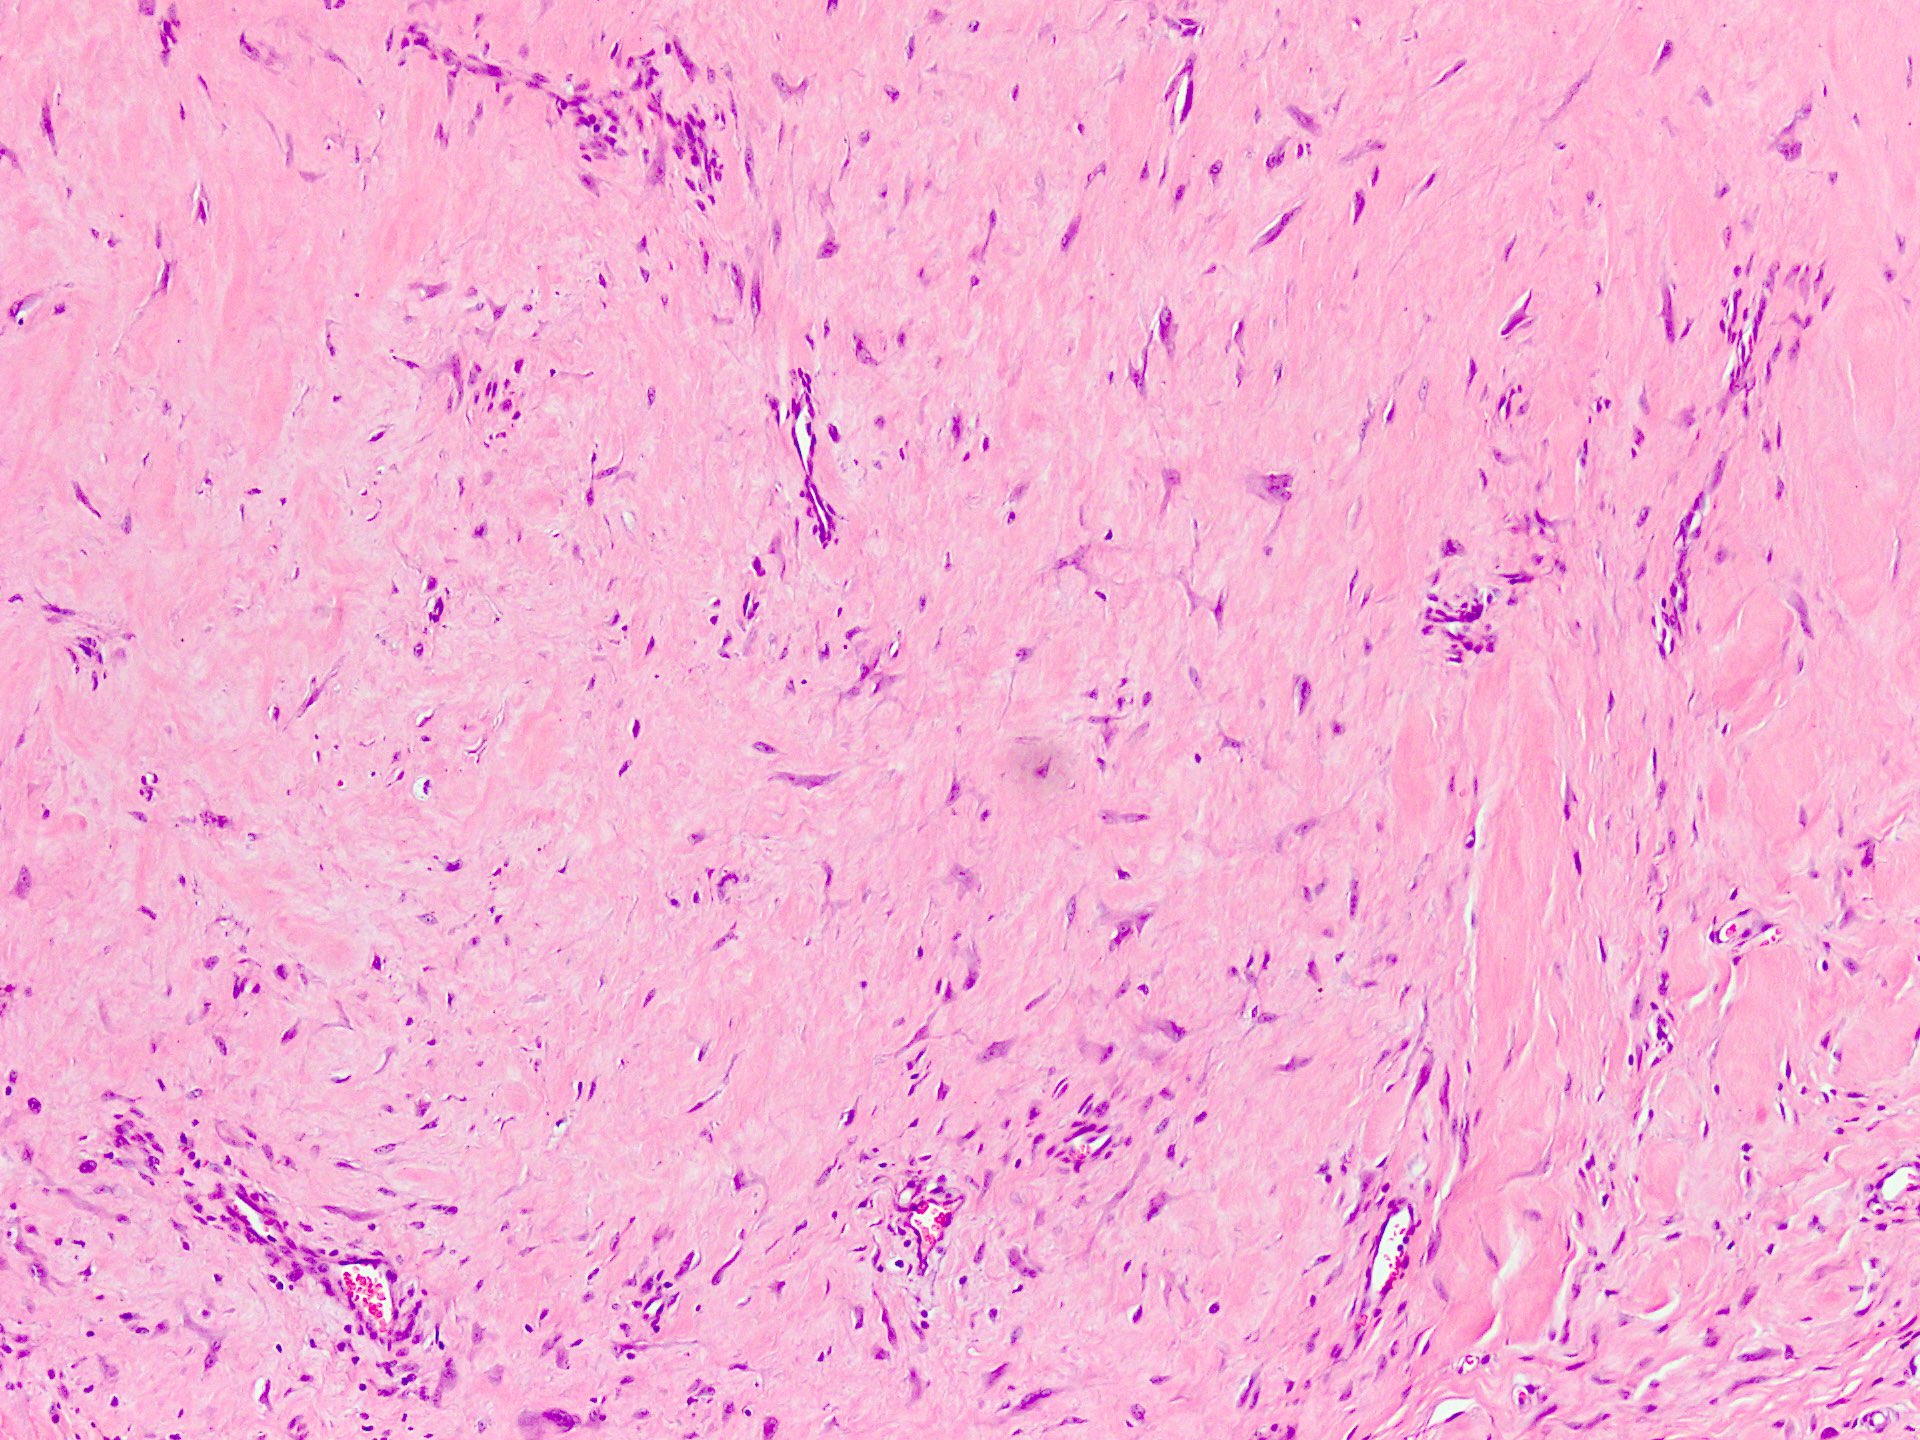

Microscopic (histologic) description

- Well circumscribed tumor of variable cellularity

- Cellularity mostly higher at tumor edges

- Bland spindle cells in a collagenous background

- Tumor has characteristic thin walled slit-like vessels

- Degenerative changes like myxoid / cystic change, osseous / chondroid metaplasia can be seen

- Bizarre pleomorphic cells can also be present

- Mitotically inactive

- Necrosis not present

- Cellular variant of fibroma of tendon sheath also exists; it overlaps morphologically with nodular fasciitis and fibrous histiocytoma (Cancer 1979;44:1945)

Microscopic (histologic) images

Contributed by Nasir Ud Din, M.B.B.S.

- Comment: Histology showed a well circumscribed, variably cellular lesion composed of bland spindle cells having regular nuclei arranged in sheets and fascicles. Thin walled vessels are present. The background is collagenous.

A 32 year old man has had painless swelling in the palm of his hand for 6 months. It was excised and the histology is shown in the above image. What is the most likely diagnosis?